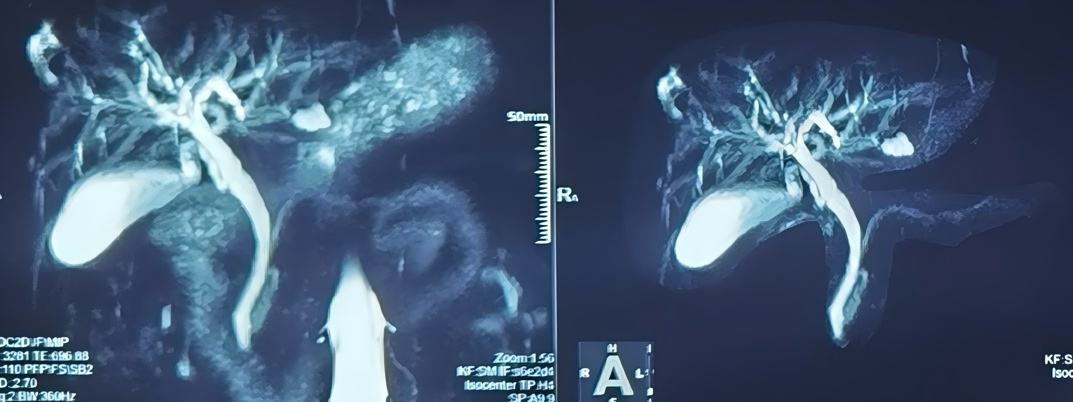

手术当天,专家团队出动“秘密武器”——直视胆道子镜系统。这台设备就像一支“微缩探险队”,沿着人体自然腔道进入胆囊和胆总管,在高清直视下锁定结石,逐一精准取出。整个手术全程体表没有任何伤口,出血量极少,杨先生全程也没有明显痛感。